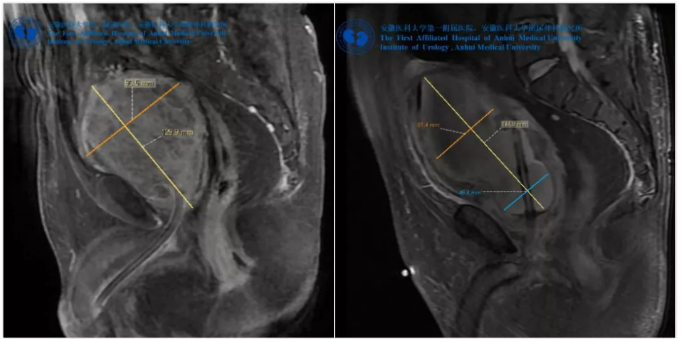

(左)术前盆腔MRI示前列腺573.7克,(右)术后第二天MRI示增生前列腺腺瘤完整去除

由于前列腺体积过大,无医院愿意为其手术治疗,后经上海某医院做了经尿道前列腺电切术,半年再后次排尿困难并出现下腹胀痛, MRI检查发现前列腺体积已经增大至573.7克,术后不到一年,前列腺体积又增加了200克以上。

手术顺利完成,患者术后膀胱冲洗一直如清水,充分体现医生的高超技艺和司迈等离子独特、可靠的止血效果,术后第二天患者即恢复正常饮食,并开始下床活动,配合完善术后盆腔MRI检测。